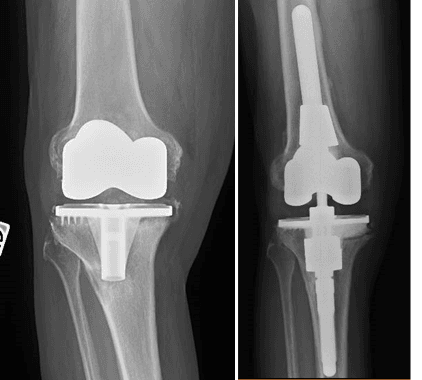

L’intervento chirurgico di revisione protesica si attua nel caso di fallimento dell’impianto primario. La revisione può essere totale (quando vengono sostituite tutte le componenti) o parziale (quando vengono sostituite solo alcune componenti), a seconda dell’entità e del tipo di problema riscontrato.

La revisione protesica rappresenta una vera e propria sfida per il Chirurgo Ortopedico, soprattutto in quei casi gravati da importante perdita del bone stock, da deficit dei tessuti molli periarticolari o in presenza di alterazioni del trofismo cutaneo, talvolta con perdita severa di sostanza, in esiti di plurimi interventi chirurgici.

Grazie ad un’esperienza chirurgica decennale nel trattamento e nella gestione di casi difficili di revisione protesica, presso il nostro centro di Chirurgia Protesica pianifichiamo accuratamente gli interventi ricostruttivi protesici, avvalendoci delle più innovative tecniche e metodiche chirurgiche (impianti protesici su misura quando necessari), ponendo particolare attenzione nell’utilizzo di materiali protesici biocompatibili che garantiscono un’ottimale osteointegrazione ed una resistenza all’usura sempre maggiore.